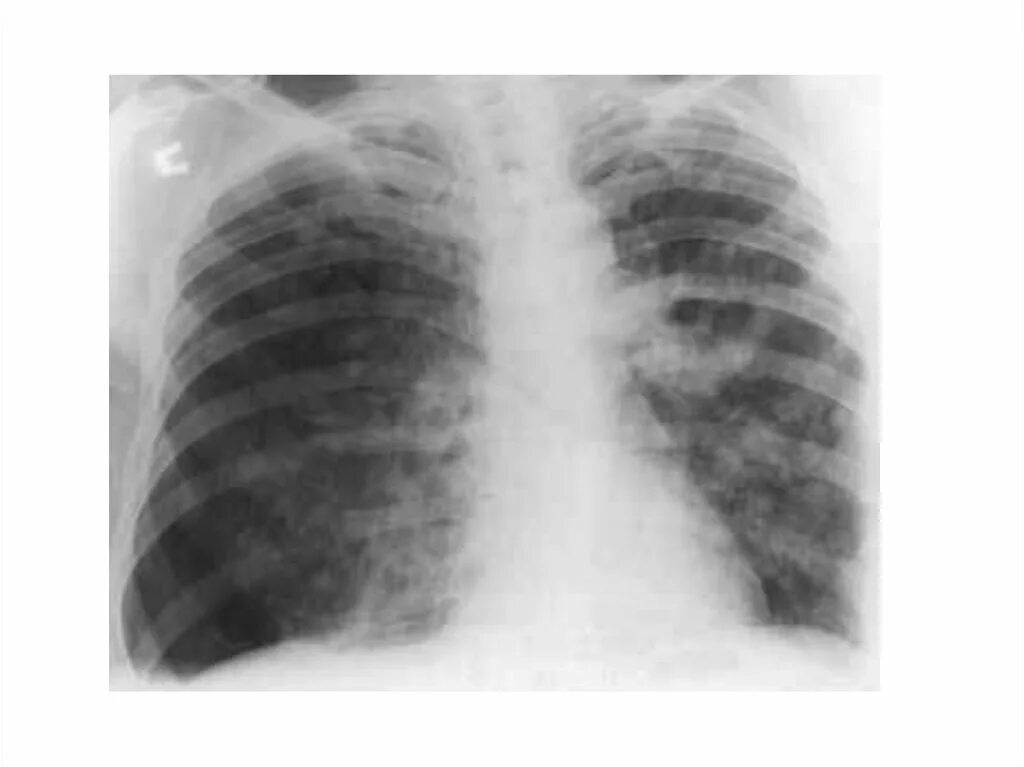

Метастазы в средостении легких